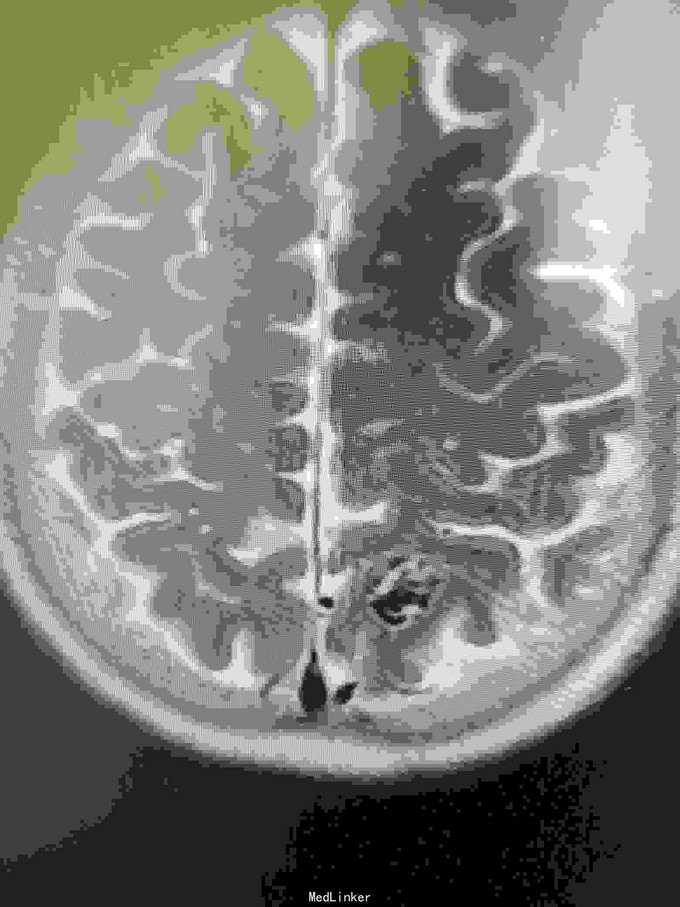

女性,65岁。入院前半年查出AvM,半年后出血入院。

神清,视力视野正常,右侧轻偏瘫。

左枕顶区AVM。 左大脑后及左大脑前供血,深部静脉回流。